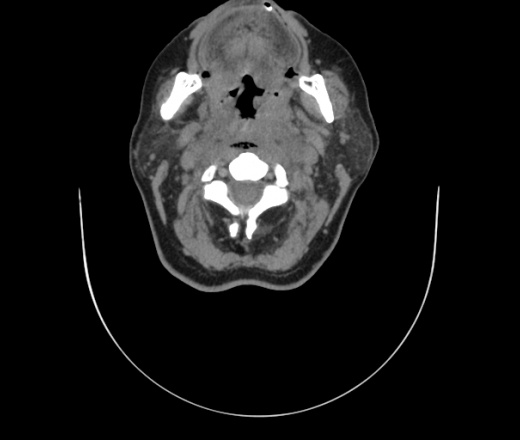

Женщина поступила в х/о спустя 4 дня после того как при употреблении карася подавилась костью.

Наличие газа в средостении на протяжении тел С2-С6 (медиастинальна эмфизема); рыбная кость на уровне тела С6.

При всем уважении, но говорить о медиастинальной эмфиземе, оценивая мягкие ткани шеи, как-то слишком резко. На мой взгляд, это ретрофарингеальное пространство.

Согласен с Вами; конечно, наличие газа в клетчатке ретрофарингеального пространства (затмение с опечаткой..). К сожалению, процесс "продвигается" к медиастиниту. Но почему никто, не отмечает наличие рыб. кости; или это для Всех очевидно?

Так вы уже отметили. Хотя ориентировал бы не скелетотопически, а на перстнечерпаловидный сустав.

Кость то мы сразу выявили, размеры где то 17*2мм, но ее так и не получается найти в этой каше